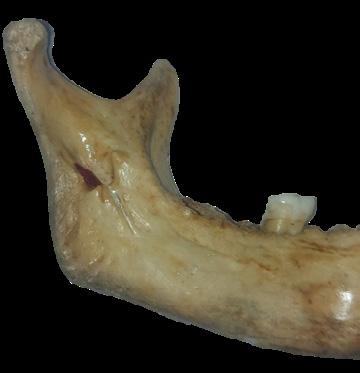

Figura 1. Cuatro formas de língulas mandibulares. Truncada (A), triangular (B), nodular (C) y asimilada (D) (8).

Figura 2. Formas de la língula en mandíbulas adultas secas. Truncada (A), presenta una forma triangular cortada en su vértice. Triangular (B), con vértice dirigido hacia el cóndilo mandibular. Nodular (C). Asimilada (D), no se evidencia la prominencia ósea lingular (8, 9).